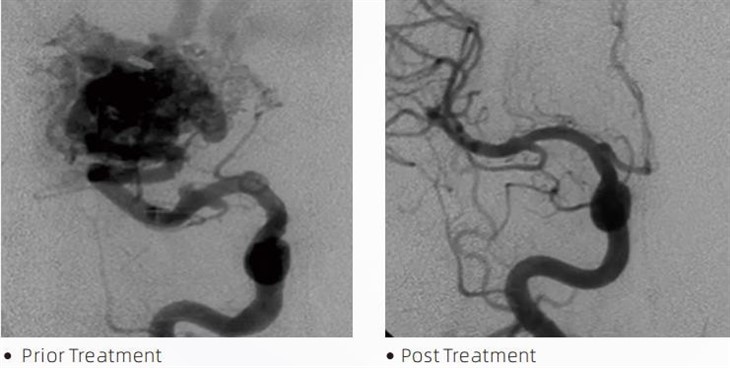

LavaMTA cola embólica é um dispositivo médico usado por neurorradiologistas intervencionistas durante procedimentos minimamente invasivos para tratar condições como aneurismas cerebrais, malformações arteriovenosas e tumores. A cola embólica Lava oferece múltiplos benefícios para profissionais médicos e pacientes em termos de segurança, facilidade de uso e eficácia. A lava é capaz de selar os vasos sanguíneos de forma rápida e eficiente. O processo envolve a injeção da cola diretamente no vaso alvo, onde ela se polimeriza e endurece em uma massa semelhante a um molde que preenche o aneurisma ou malformação. Em seguida, ele corta efetivamente o fluxo sanguíneo para a lesão, evitando que ela se rompa e reduzindo o risco de danos permanentes ou derrame. Lava inclui Lava-12, Lava-18 e Lava-34. Cada formulação é projetada para atender necessidades clínicas específicas. Lava-18 é uma formulação padrão para uso geral. Lava-34 é uma cola de alta viscosidade para vasos de alto fluxo. Enquanto o Lava-12 tem uma viscosidade mais baixa e é mais fluido, permitindo microvasos distais. Com essas opções, os neurorradiologistas intervencionistas podem escolher as formulações de Lava adequadas para garantir resultados ideais. Uma das características mais notáveis da Lava são as suas propriedades não adesivas. Esta substância é especialmente formulada para permanecer estável até atingir a área alvo. Esta característica significa que a cola embólica Lava pode ser colocada com precisão dentro da artéria e permanecer lá sem aderir ou aderir ao tecido circundante.